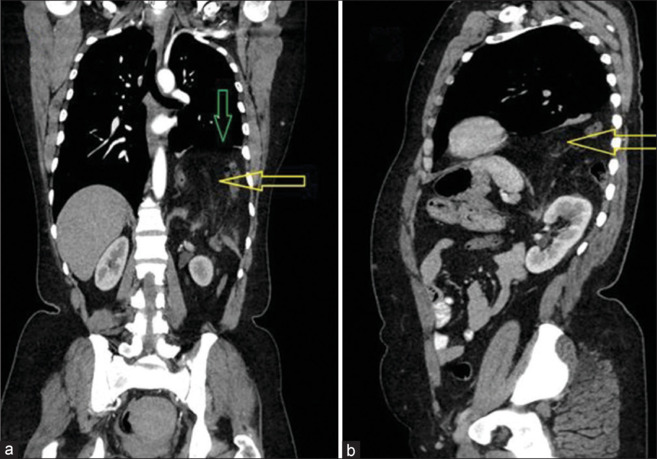

先天性膈疝(CDH)和获得性膈疝(ADH)继发于膈肌无力或开口。两者都是内疝的类型。这种异常的范围可以从膈肌后缘的一个小缺陷到整个膈肌的丧失。CDH通常导致肺发育不全,伴有肺动脉高压和不成熟,以及心功能障碍。在ADH中,病理生理是继发于疝出及其压力效应。我们报告了两例自发性ADH (SADH)。自发性获得性膈肌破裂可发生在运动、咳嗽、分娩后,甚至在没有任何明显的前期事件的情况下。尚不确定SADH是由膈肌先前存在的薄弱区域引起的,还是由于剧烈运动时肌肉协调性的丧失,或两者兼而有之。这是一种潜在致命的外科急诊,需要在适当的临床环境中进行高指标的临床判断。SADH通过压迫肺来机械地起作用。这是一个罕见的实体。本病例系列和回顾简要说明自发性膈疝的发生、诊断和治疗。

Congenital diaphragmatic hernia (CDH) and acquired diaphragmatic hernia (ADH) are secondary to a weakness or opening in the diaphragm. Both are types of internal hernia. The abnormality can range from a minor defect in the posterior edge of the diaphragm to the entire loss of it. CDH usually leads to lung hypoplasia associated with pulmonary hypertension and immaturity, as well as cardiac dysfunction. In ADH, pathophysiology is secondary to herniation and its pressure effects. We report a series of two cases of spontaneous ADH (SADH). Spontaneous acquired rupture of the diaphragm can occur after exercise, coughing, labor (delivery), or even without any significant preceding event. It is uncertain if SADH is caused by a preexisting weak region in the diaphragm, a loss of muscle coordination during vigorous exertion, or both. It is a potentially fatal surgical emergency requiring a high index of clinical judgment in the appropriate clinical setting. SADH acts mechanically by compressing the lung. It is an infrequent entity. This case series and review concisely illustrate the genesis, diagnosis, and treatment of spontaneous diaphragmatic hernia.